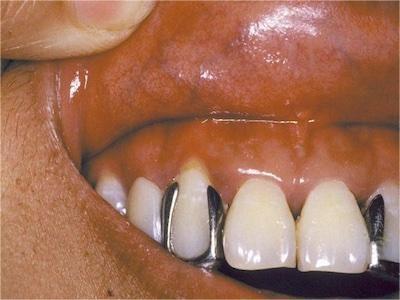

过敏性接触性口炎患者接触变应原后,经2-3天在接触部位发生病变,轻者黏膜肿胀发红,或形成红斑。重者发生水疱、糜烂或溃疡,甚至组织坏死。病变除在接触部位外,也可向邻近部位扩展。口腔科临床常见为修复材料引起的过敏性接触性口炎。

过敏性接触性口炎除了局部使用药物这一病因外,主要为充填和修复材料引起,如银汞合金、自凝塑料等。本病的发病多为Ⅳ型变态反应。